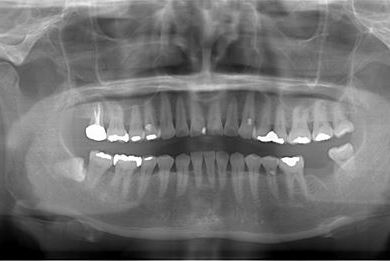

性別/年齢 女性 / 54歳

主訴 抜歯したところのインプラント治療を希望。

治療内容 インプラント1本、メタルボンドセラミック1本

総治療費 252,000円

治療期間 4ヶ月

治療前

治療後